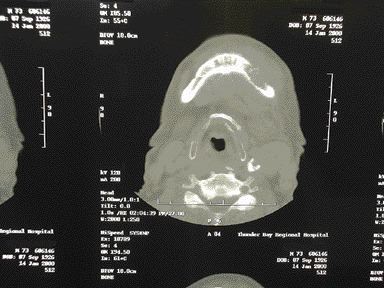

A Review of Oral Metastatic Disease

FIGURE 2--CT scan of the inferior aspect of the mandible. Axial view shows a lytic defect approximately 2 cm. in diameter with a fracure in the lingual cortex.

By Tim D. Sands, DDS, Dip OMFS and Bruce R. Pynn, Msc, DDS, FRCDS(C) Oral malignant metastases are a relatively rare finding considering the incidence of metastatic tumors in the body. They account for less than one percent of all metastatic malignancies, which prefer to spread to the spine, pelvis, skull or ribs.1 Most oral … Read more